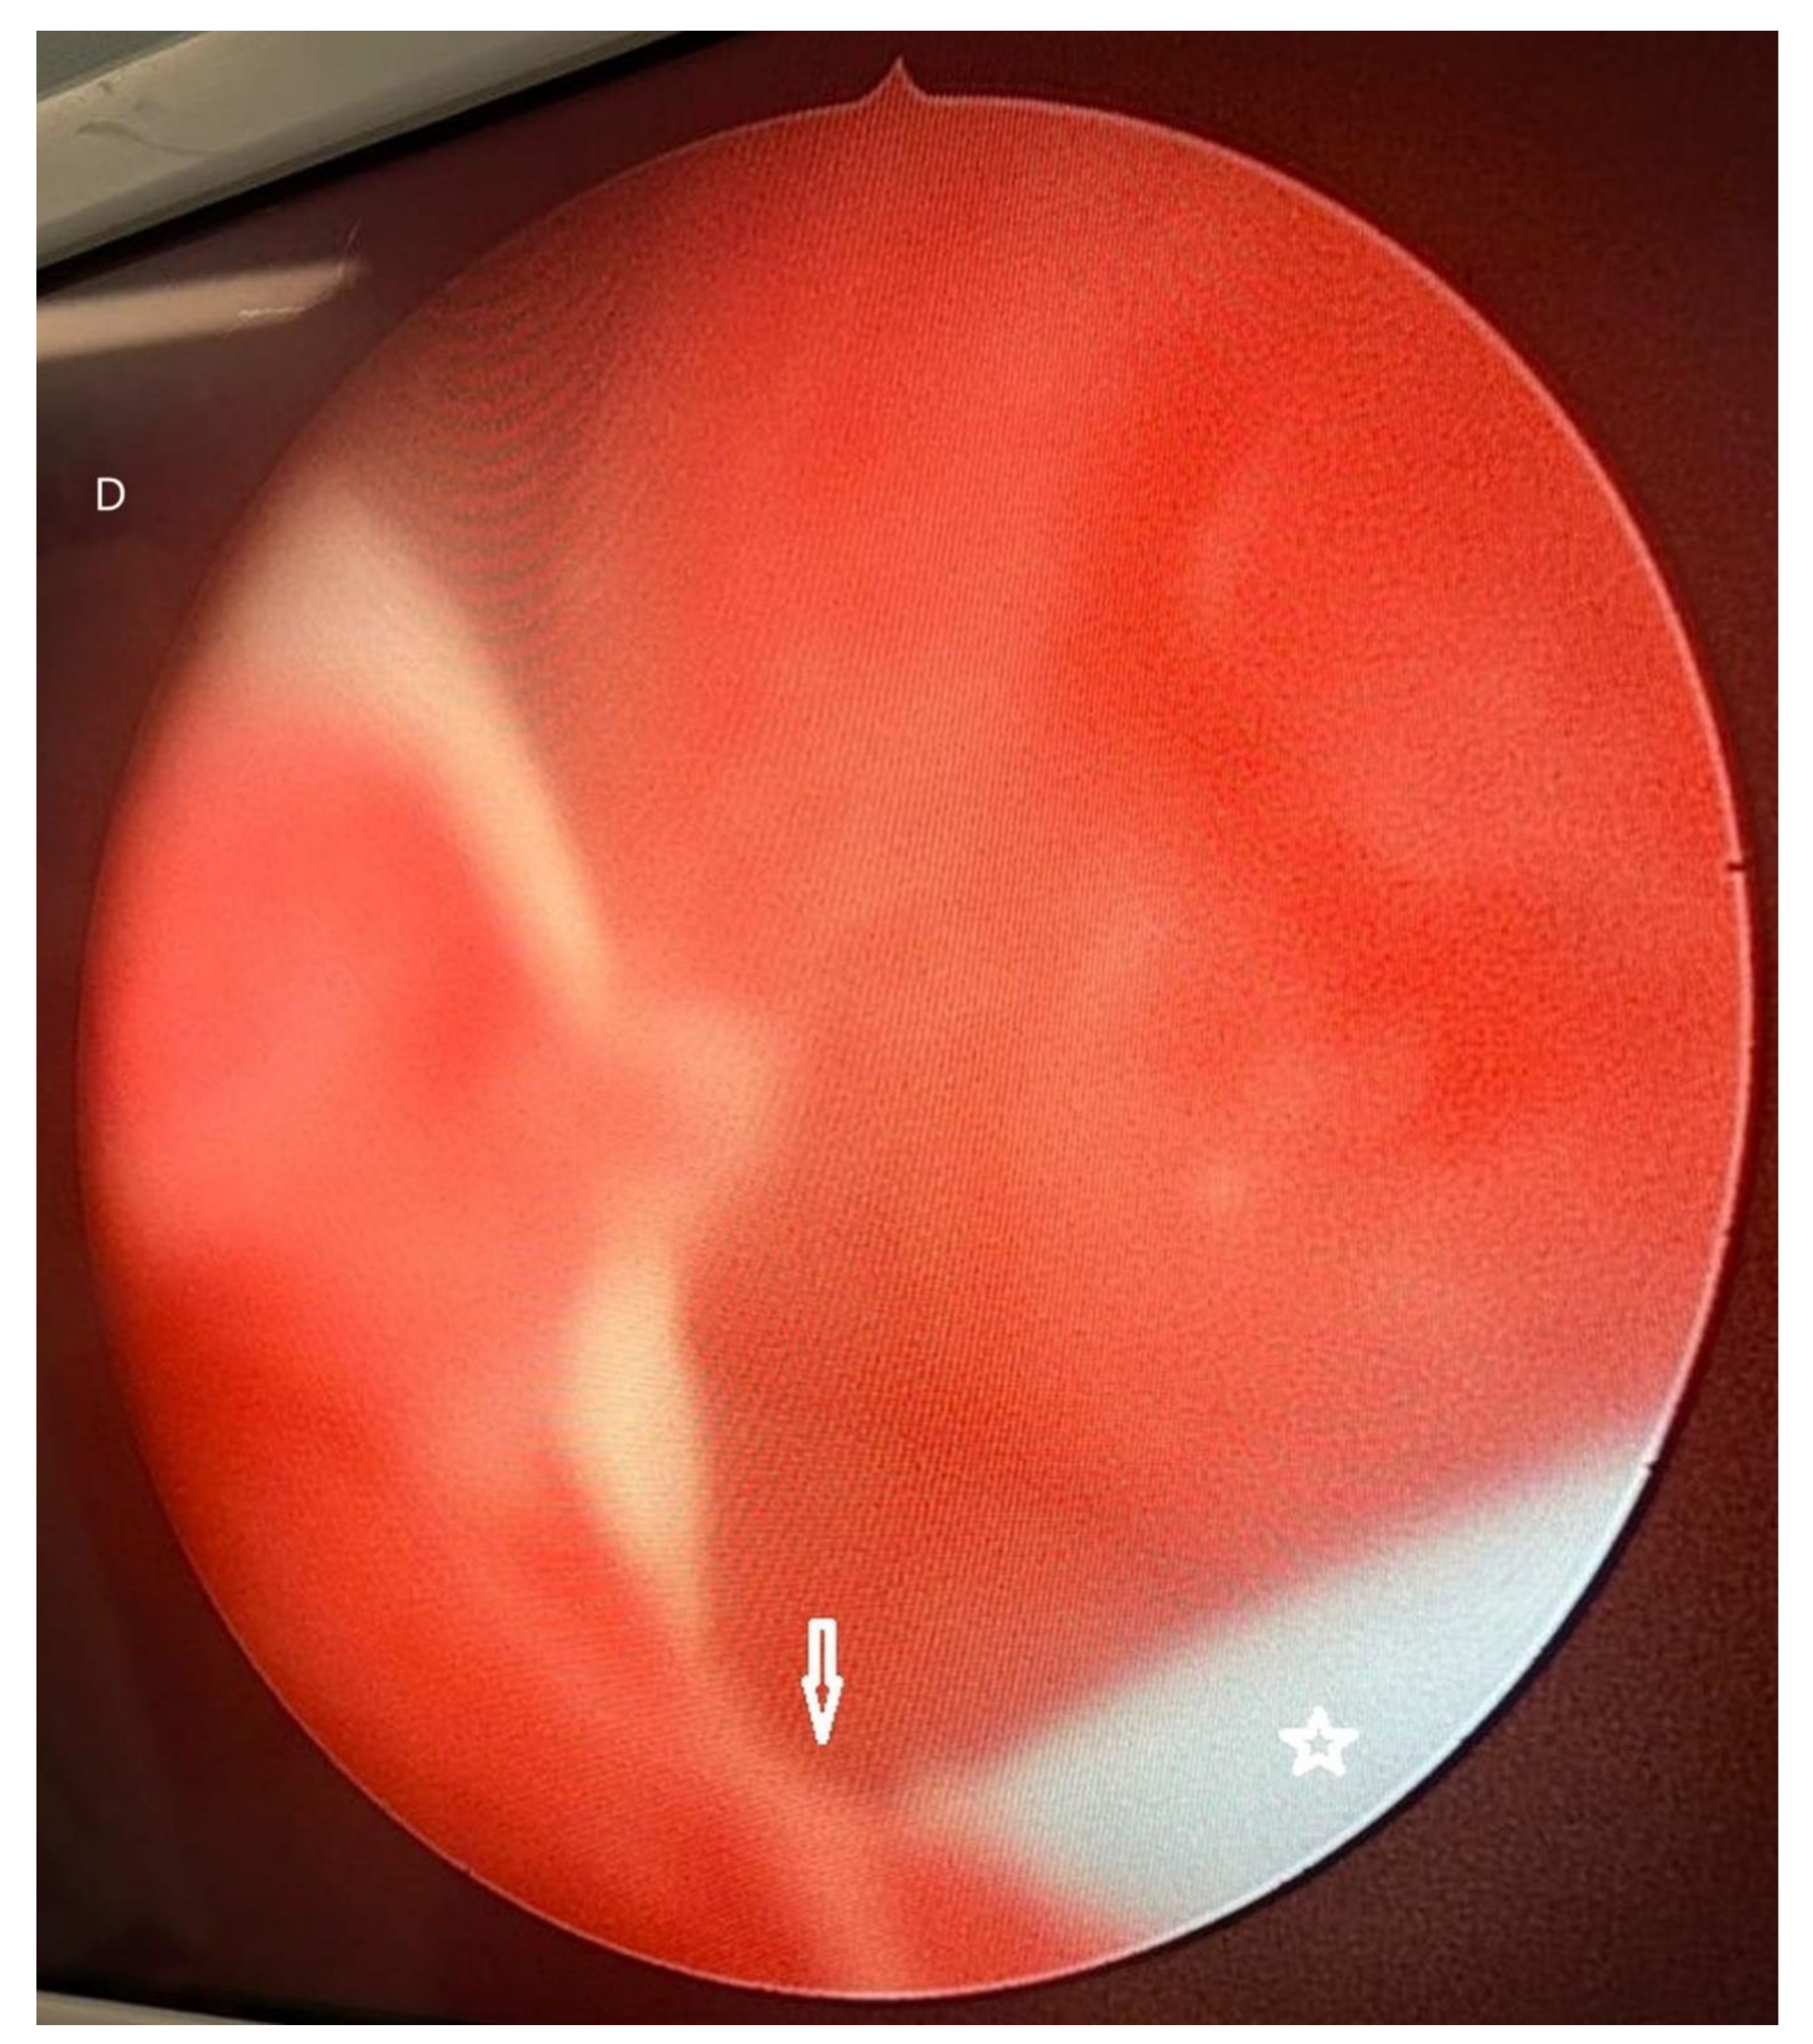

CT scan (non-contrast) detected moderate bilateral hydronephrosis (Figure 1 A), intraluminal gas in urinary bladder with thickened walls indicative of emphysematous cystitis (Figure 1 B). At cystoscopy, a whitish mass filling up the urinary bladder was found. While the mass was being resected with resectoscope (Figure 1C), the mass extruded in toto into the vagina through a vesico-vaginal fistula (Figure 1 D). The histopathological report demonstrated predominantly necrotic material, fungal organism in the form of spores and hyphae. PAS and GMS stain were positive for fungal organism. Ultrasonography repeated after 14 days of Fluconazole showed resolution of hydronephrosis. Patient was scheduled for repair of the fistula but she did not report for the repair.

Figure 1. D: Cystoscopy after removal of fungal mass: vesico-vaginal fistula (down arrow) with a blue 5 F ureteric catheter (star) in the fistula.